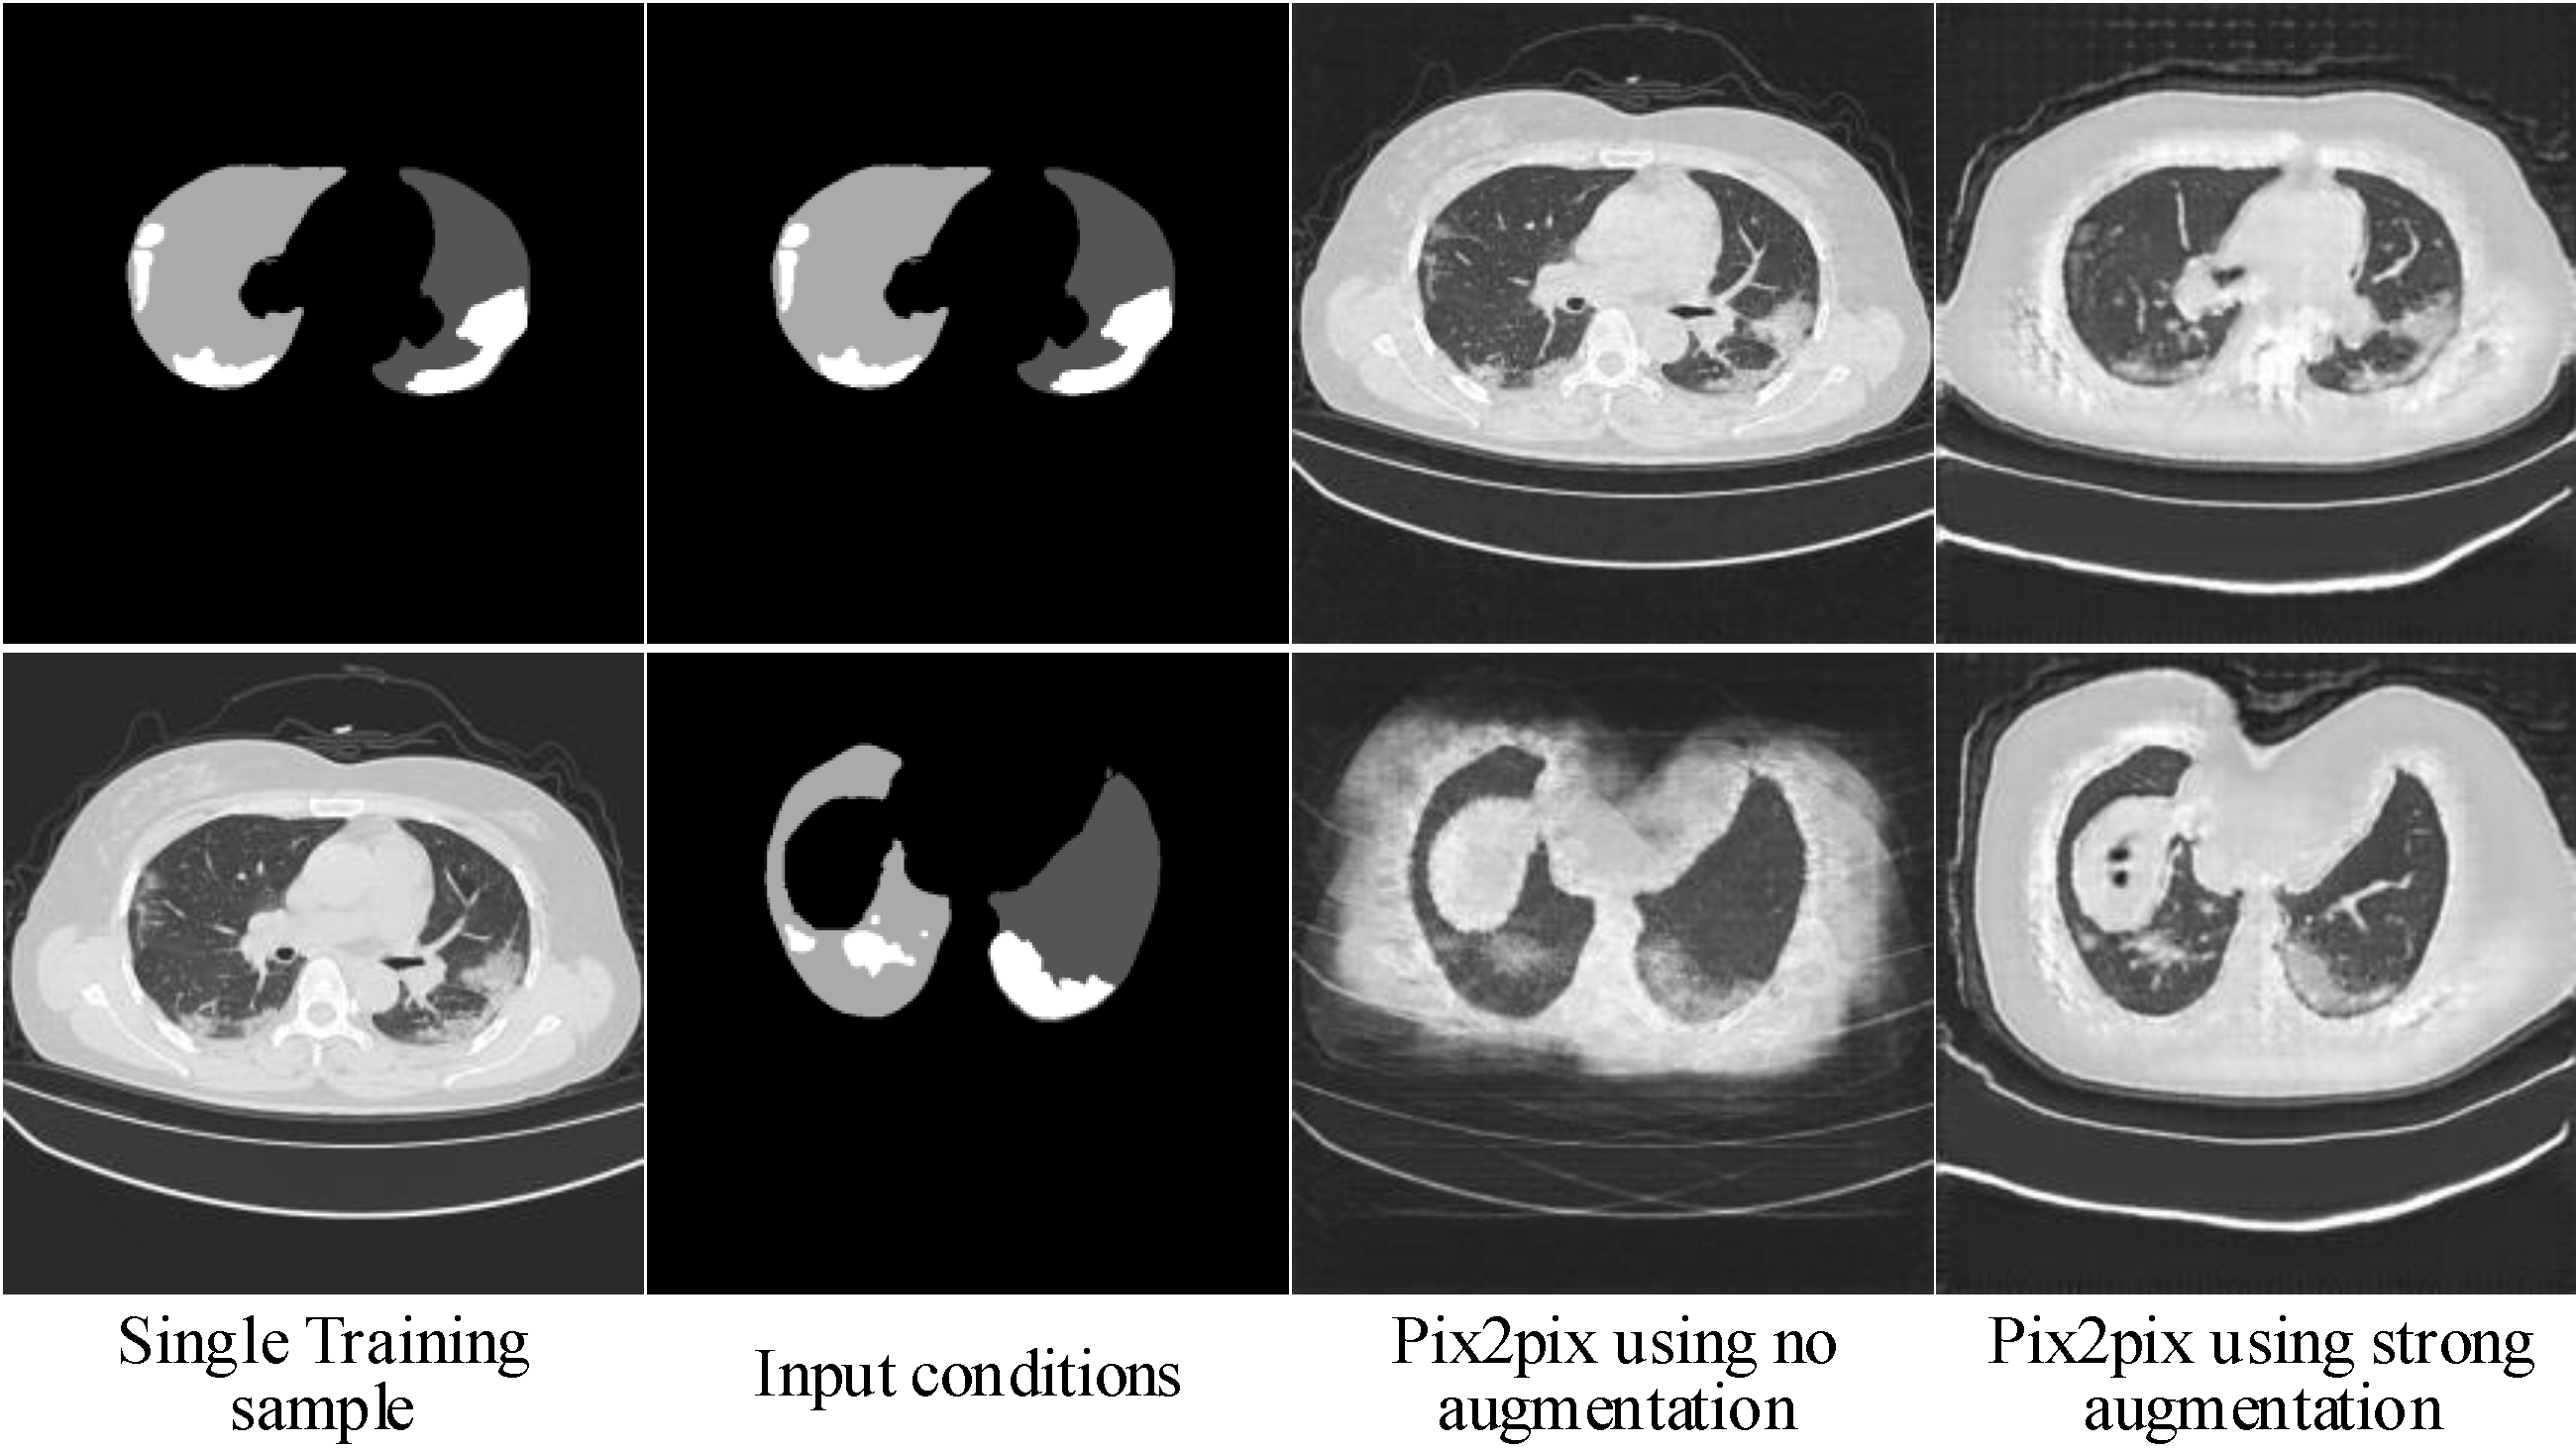

2.1.3. Hierarchical Data Augmentation

- SA is critical for to generalize to different input conditions.

- WA helps to fit the real image distribution without introducing additional learning burden.

- Decreasing the intensity of SA along with the increasing of image scales can handle the balance between fitting conditions and fitting images well.

3.1.2. Ablation Experiments